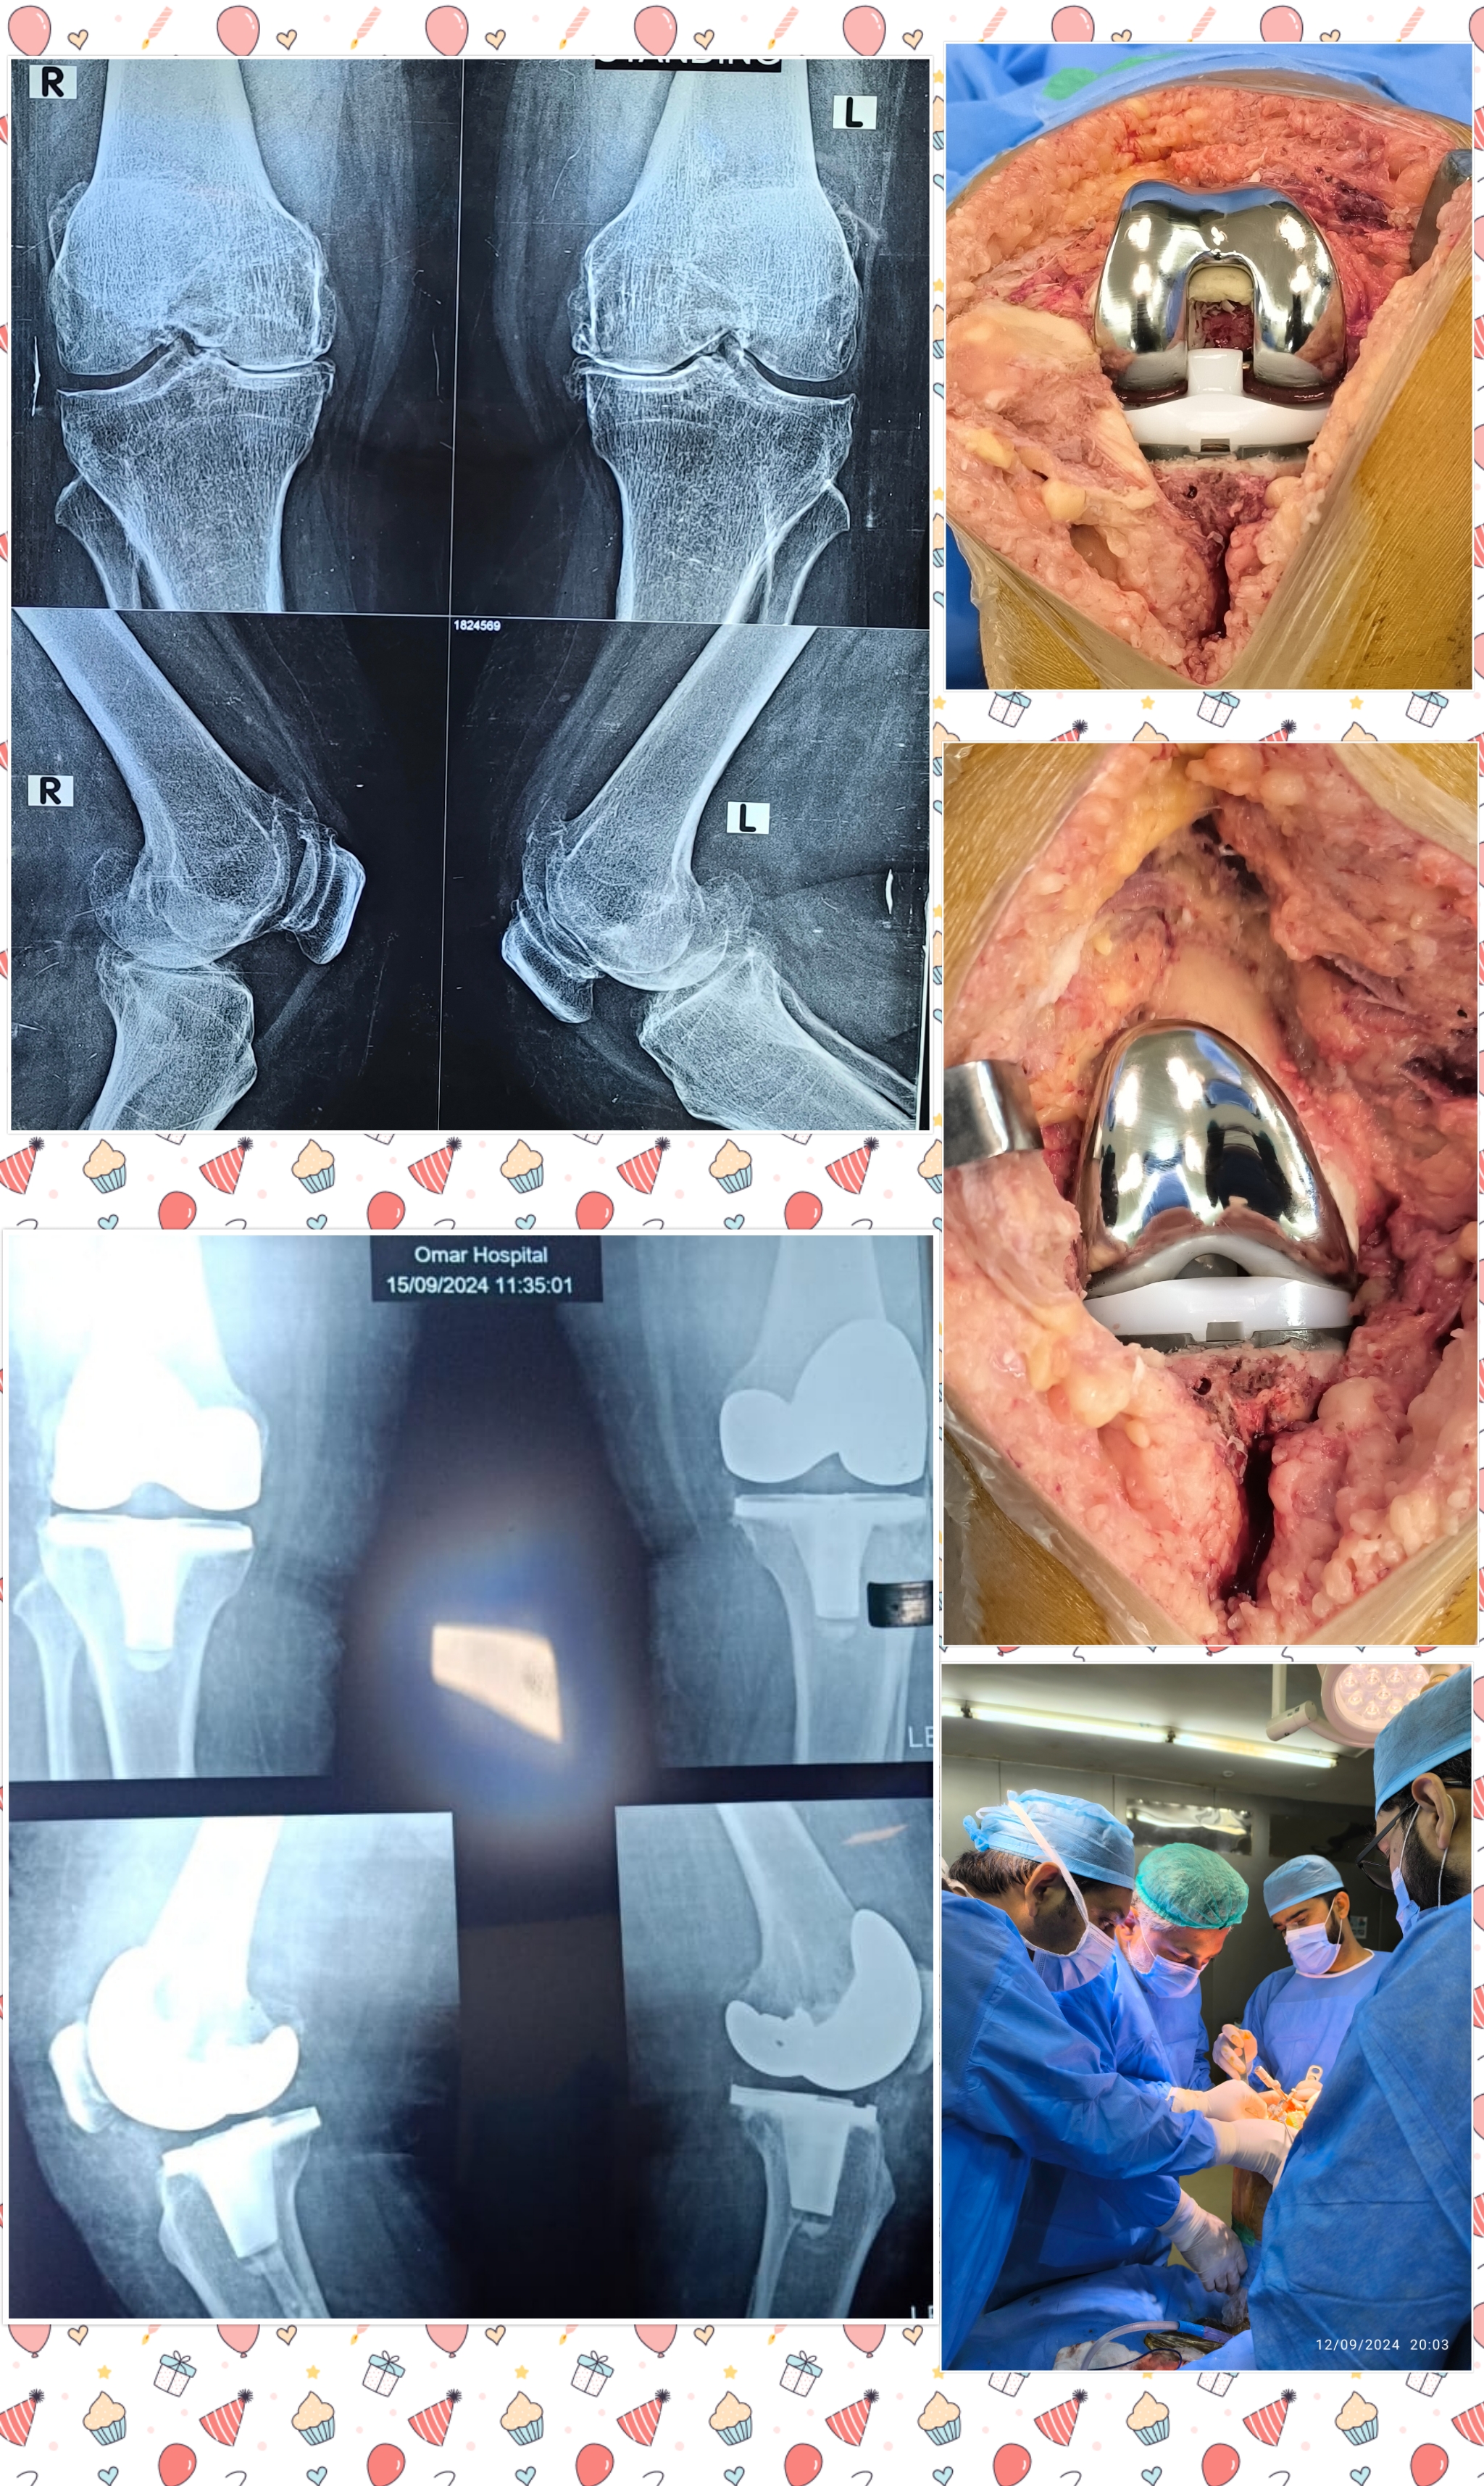

Warning: Graphic Content

The following section contains graphic images of surgical procedures. These images are intended for educational purposes and may be disturbing to some viewers. Viewer discretion is advised.

Surgeries